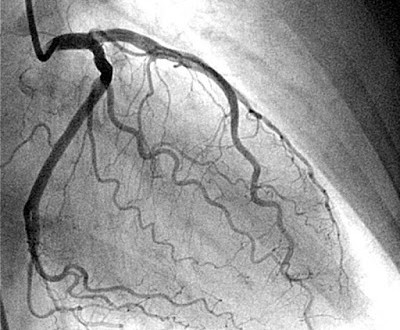

Στεφανιογραφία: Εδώ, ένας μικρός καθετήρας εισέρχεται από κάποια επιφανειακή αρτηρία και προωθείται στην καρδιά όπου ενίεται σκιαγραφική ουσία. Με τον τρόπο αυτό απεικονίζεται η καρδιά και τα αγγεία της και φαίνεται αν υπάρχει απόφραξη στις στεφανιαίες αρτηρίες.